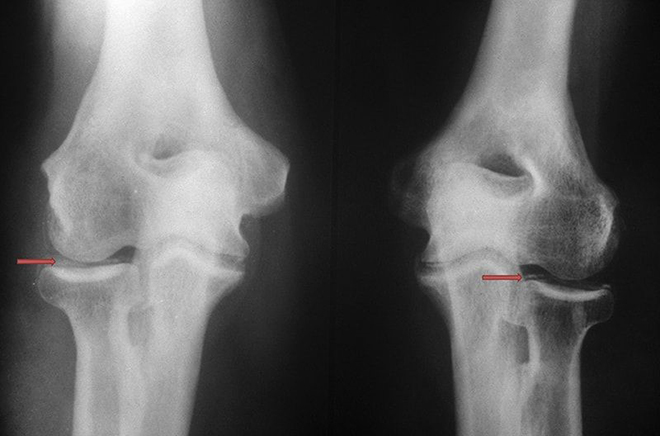

Hình ảnh X-Quang thoái hóa khớp gối

Khi bệnh tiến triển đến giai đoạn nặng, hai đầu xương có thể đối đầu và va vào nhau khi bệnh nhân di chuyển. Lúc này bệnh nhân không chỉ có cảm giác đau nhức mà còn có tiếng kêu lục khục